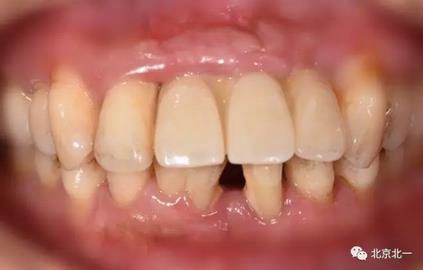

圖六:戴牙后口內(nèi)照,患者笑線低。未做牙齦誘導(dǎo)也不太影響容貌。簡化治療程序節(jié)省患者時間成本以及金錢成本。

圖七:微笑時照片